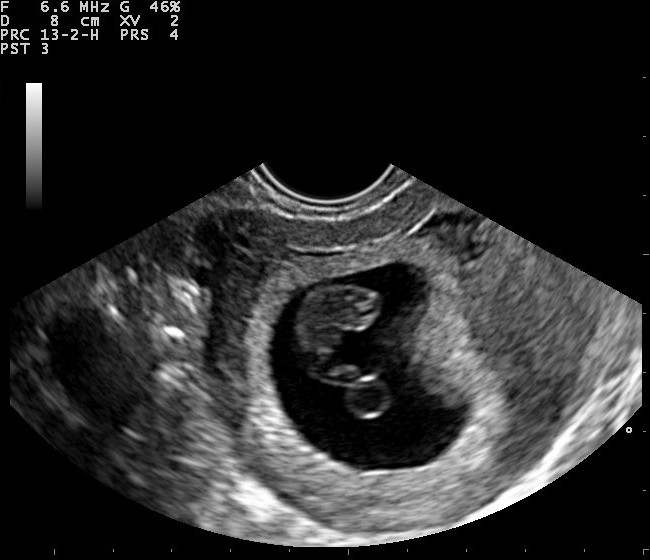

산부인과 초음파 검사는 임신을 확인하고 진단하는 데 사용될 수 있다. 초음파 검사 전에 가정용 소변 임신 테스트에서 양성 반응을 보이는 경우가 많다. 복부 초음파와 질 초음파 모두 사용될 수 있지만, 질 초음파를 사용하면 더 이른 시기에 임신을 확인할 수 있다. 산부인과 초음파 검사를 통해 임신낭(자궁 내 체액 덩어리)은 임신 4.5~5주에, 난황낭은 임신 5~6주에, 태아 극은 임신 5.5~6주에 시각적으로 확인할 수 있다. 초음파는 소변이나 혈액 내 hCG의 존재만으로는 진단할 수 없는 다태 임신을 진단하는 데 사용된다.[15] 배아/태아의 임신 주수를 결정하는 것은 hCG 검사와 비교했을 때 초음파 검사의 또 다른 장점이다.[16]3. 임신 진단 검사의 정확도